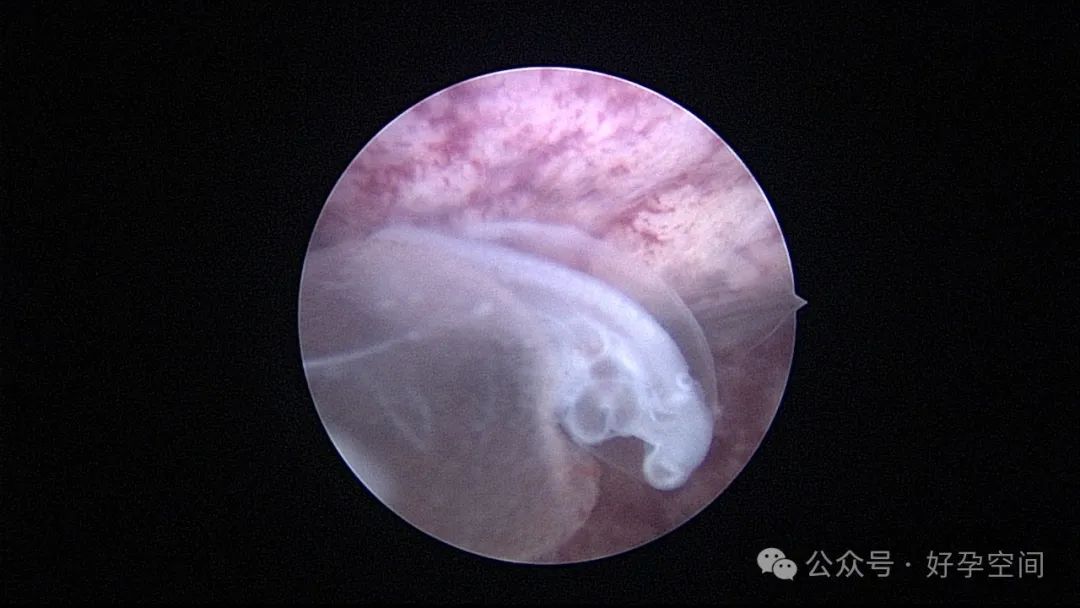

宫腔镜下的胚胎图解

宫腔镜下的胎儿(自妊娠第11周,即受精第9周起称为胎儿)